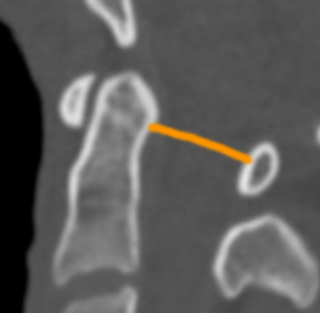

Image Type Cervical Spine X-Ray CT Scan MRI Scan Atlantodental Interval (ADI) Basion–Axial Interval (BAI) Basion–Dens Interval (BDI) Canal Occupying Ratio (COR) Clivo-Axial Angle Facet Joint Overlap (Percent Overlap Method) Facet Joint Step-Off/Dislocation Grabb-Oakes Measurement (pB - C2 line) Occipital Condyle–C1 Interval (CCI) Posterior Atlantodental Interval (PADI) Power’s Ratio Sagittal Vertical Axis (SVA) Segmental Angle Translation on Sagittal Reconstruction